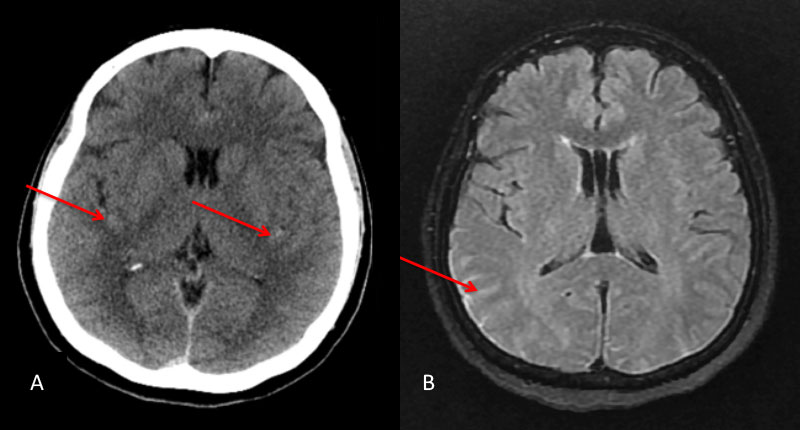

A man in his 60’s presented with acute onset of abdominal pain radiating to the back. The initial evaluation focused on GI abnormalities which were unremarkable. A screening CT scan of the brain was performed and suggested a possible subarachnoid hemorrhage which was subsequently confirmed on MRI and lumbar puncture (Figure 1A and 1B).

Figure 1: A) Non Contrast CT and B) MRI FLAIR studies demonstrate subtle Subarachnoid hemorrhage in the sylvian and parietal sulci (arrows)